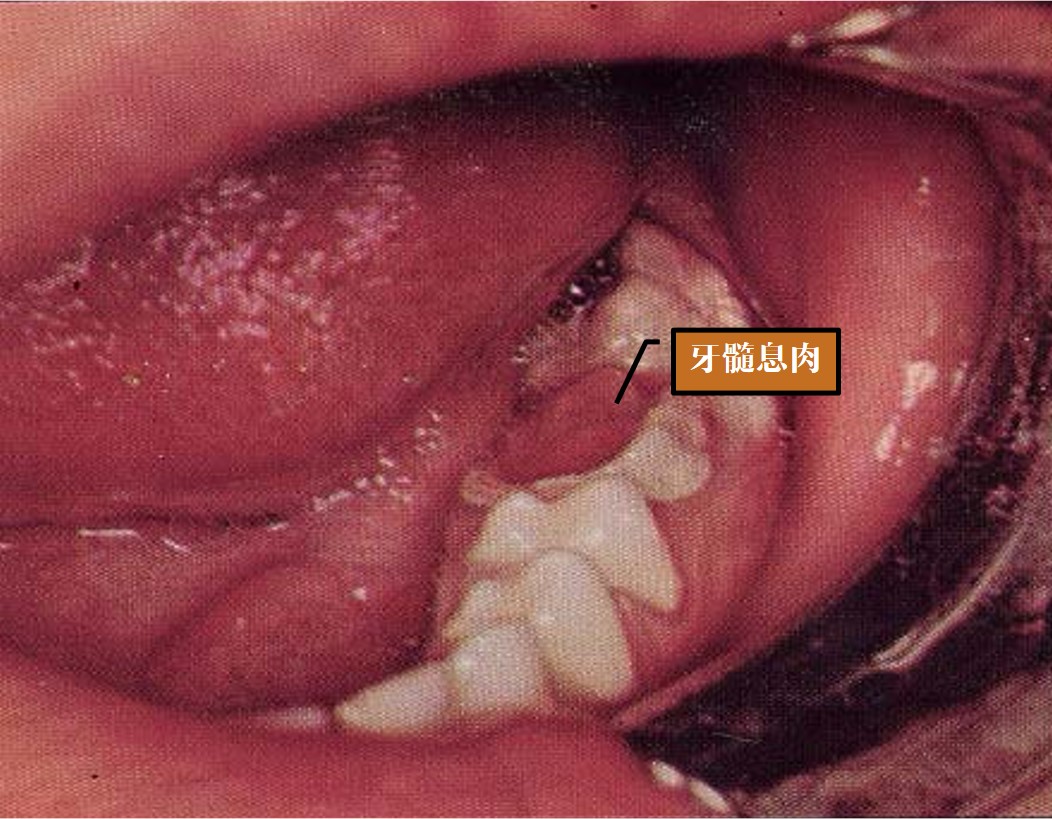

3)慢性增生性牙髓炎(Chronic hyperplasticpulpitis)

又称牙髓息肉。

a.临床表现

无明显疼痛,息肉米粒大小或充满整个龋洞(图8.1-6),进食时易出血或轻微疼痛,冷热刺激表现钝痛,探痛不明显。

图8.1-6 牙髓息肉